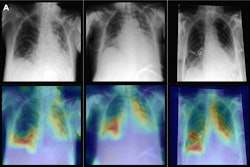

Yet studies evaluating AI chest x-ray algorithms may be where the rubber meets the road, with developers able to leverage larger patient datasets than with other modalities. In one study, for instance, researchers used chest x-rays from 7,105 patients to develop a deep-learning model that predicts 30-day mortality in patients with community-acquired pneumonia.